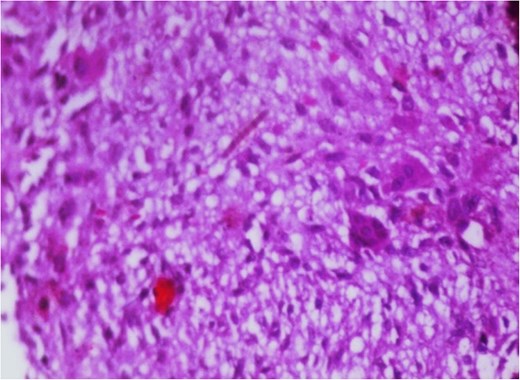

Additionally, magnetic resonance venography (MRV) confirmed a patent superior sagittal sinus with no encroachment of the lesion (Fig. 4). Differential diagnoses included dermoid cyst, eosinophilic granuloma, or benign fibro-osseous lesion. Surgical intervention involved en bloc excision under general anesthesia. A curvilinear incision was made over the mass, followed by subperiosteal dissection, which confirmed the lesion’s confinement to the diploë. Intraoperative frozen section analysis was not performed due to the lesion’s benign radiological features. Histopathological examination confirmed NOF, demonstrating ectodermal inclusion, cellular stroma of spindle-shaped fibroblasts arranged in a prominent storiform pattern, and scattered osteoclast-like giant cells. Notably, no evidence of mitotic figures, nuclear atypia, or necrosis was observed (Figs 5–7). The margins were free of lesional tissue. Postoperatively, the child resumed oral intake within 4 hours and was discharged on postoperative day 2 with analgesics. At the 6-month follow-up, the wound had healed without complications, with no recurrent lesion.

Photomicrograph in a case of NOF showing interlacing bundles of spindle-shaped fibroblasts in a storiform manner, H&E × 400.

Photomicrograph in a case of NOF showing osteoclast-like giant cells, H&E original magnification × 400.